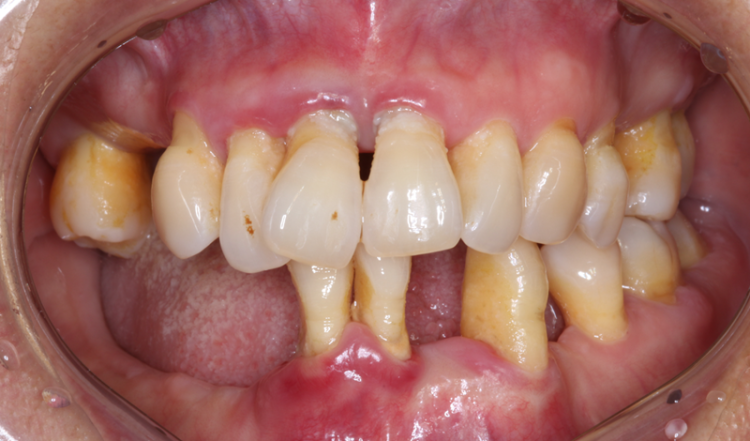

이런 현상이 개선되지 않고 계속 반복되면 점점 잇몸 내려앉음이 발생하고 튼튼하게 잇몸뼈를 지지해 주던 잇몸뼈가 녹아내려 치아도 약해지고

심한 경우엔 발치를 하게 되는 것인데요. 이렇게 치석이 깊게 침투한 상태에서 스케일링을 받아도 치아 표면인 겉만 청소가 될 뿐 잇몸 속은 여전히 치석이 가득 차 있어 아무리 양치를 꼼꼼히 해도 잇몸 염증이 낫지 않고 잇몸 내려앉음이 발생하게 되는 겁니다.

3232235521_yfE4sIRU_08daebcef9958e840d4215cc0abc43efedaa4eaa.png 그럼 잇몸 내려앉음이 더 이상 진행되지 않도록 막으려면 잇몸 속 치석을 제거하는 것이 가장 첫 번째로 해야 할 치료가 되겠죠? ​

그러나 기존의 치료 방법들은 메스로 잇몸을 절개를 해서 수기구로 치석을 제거하는 방식이라 통증과 회복 기간도 상당하게 발생하는데

더 위험한 것은 잇몸뼈가 공기 중에 노출되면 뼈가 녹는 속도가 훨씬 빠르고 잇몸이 약해지기 때문에 좋은 결과를 기대하기는 어렵습니다. 3232235521_UMJFRCEv_1ae2fad53fafee3cb764ae2ee81e54d4db3ad922.png 그렇다면 잇몸 속 치석을 방치하고 잇몸 내려앉음이 발생하는데도 손 놓고 기다려야 하는지 마음이 안 좋으실 텐데요. 3232235521_IaTqZzGP_4055b8d6ace5f5edbe40d099fe24107132a7aa88.png